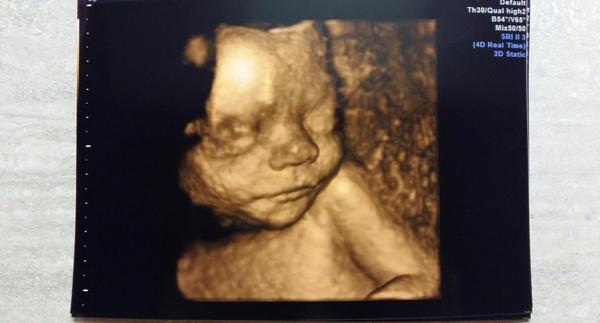

Holky my zas byly s manželem na 4d ultrazvuju a jsme naprosto ohromení 😍😃. Naše prďolka se nám krásně předváděla. 😃 Je to neuvěřitelné vidět miminko ještě dříve než se narodí. Moc moc se na ni tešíme. Jen mě tedy pohltil strach o ní, přeci jenom ješte 3 měsíce chjo už bych ji chtěla mít v pořádku u sebe.

@elenadavis Plánujete také takový ultrazvuk nebo jste už některá dříve byla? Já už jsem viděla jak takový ultrazvuk vypadá, ale vidět ho na živo a ten pocit že jde o vaše miminko byl opravdu zážitek. I manžel uronil slzu byly jsme z toho úplně paf 😃😂😉😍 Jediné mínus byla cena, ale za ten zážitek, fotky a video nám to rozhodně stálo. 🙂